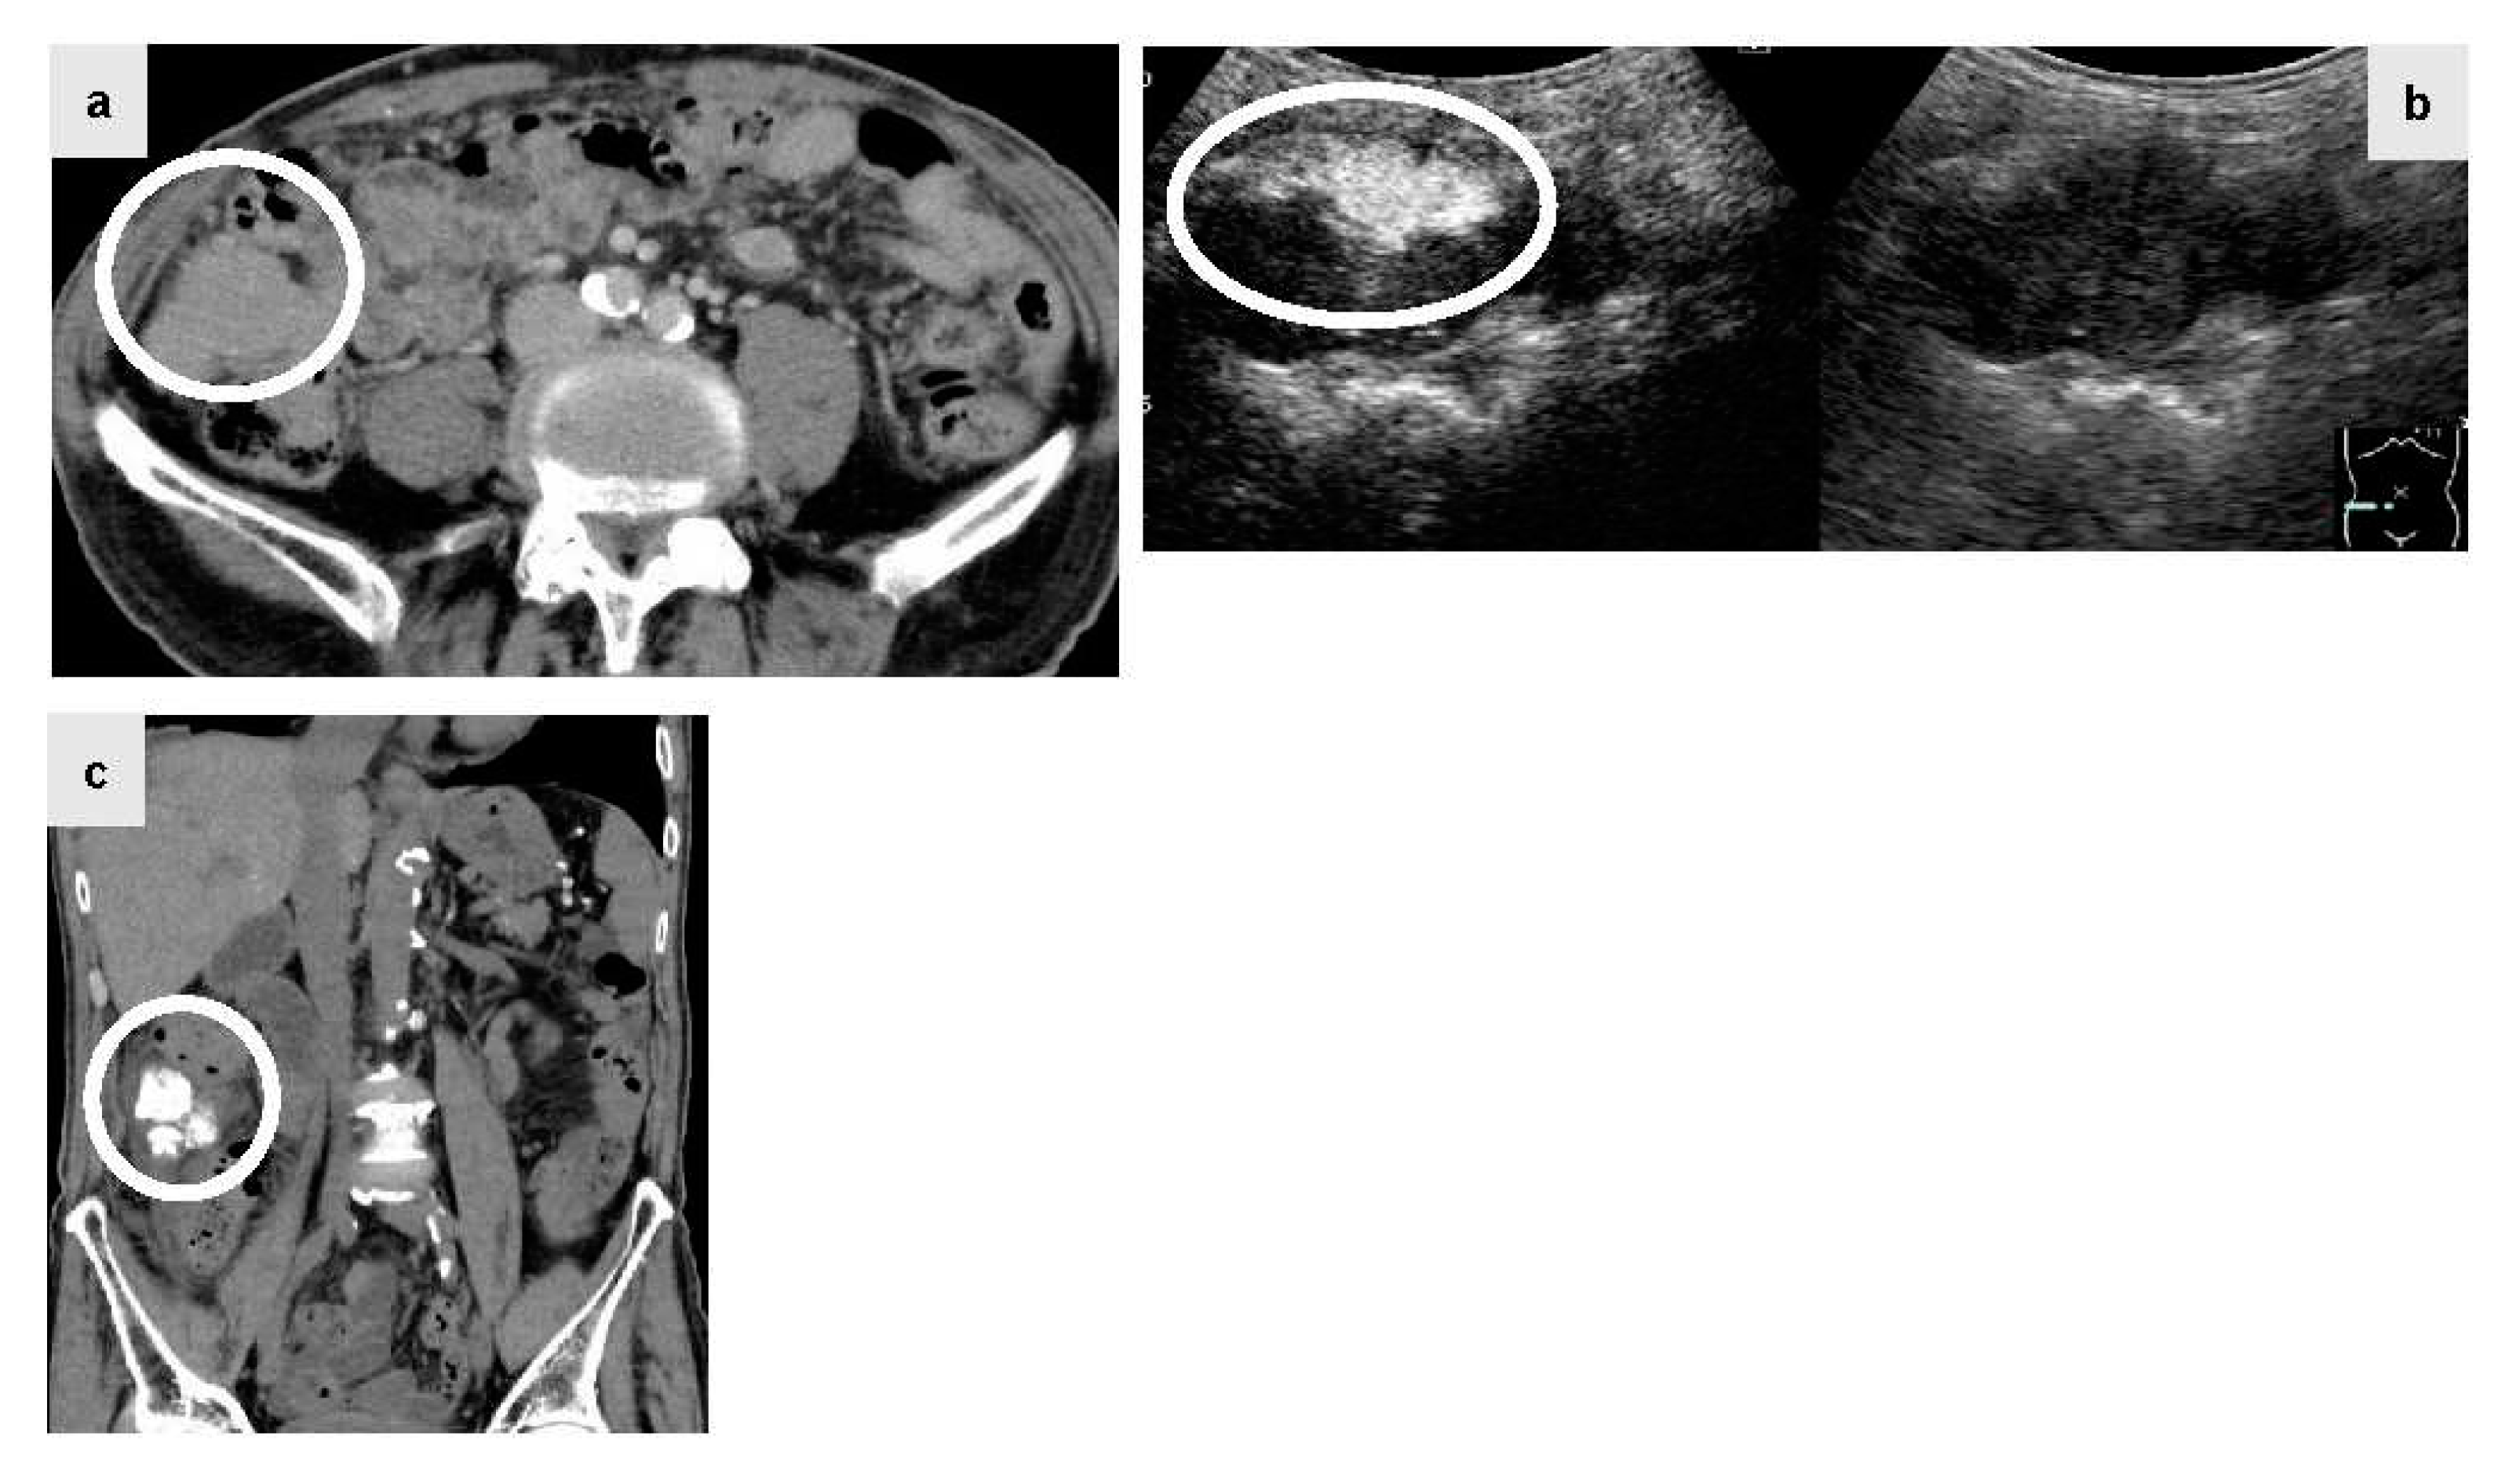

The patient was a male in his 80s with hepatitis C virus-related cirrhosis who developed a disseminated lesion with a diameter of 55 mm close to the ascending colon by plain CT (Figure 2a, circle) 1.5 years after RFA for primary HCC. Lenvatinib (40mg q.d.: quaque die) was administered at a decreased dose due to proteinuria, but was discontinued since there was no reduction of the disseminated lesion. Since the lesion was large and connected to the intestinal tract, abdominal angiography using IAUS was performed. Gastroduodenal arteriography suggested that the disseminated lesion was supplied by two epiploic branches. A selective contrast study confirmed tumor staining in both of these branches. IAUS for each branch showed contrast enhancement in the disseminated lesion, but no enhancement of the adjacent intestinal tract wall (Figure. 2b, circle) (Right image: monitor mode). Thereafter, TACE using ELE and Gelpart® was performed for the individual branches. Plain CT after TACE showed accumulation of Lipiodol® only in the disseminated lesion (Figure. 2c, circle). Readministration of lenvatinib after TACE was suspended due to redevelopment of proteinuria and decreased activities of daily living. Concomitant therapy of atezolizumab (Chugai Pharmaceutical Co., Ltd. Tokyo, Japan) and bevacizumab (Chugai Pharmaceutical Co., Ltd. Tokyo, Japan) was started, but discontinued due to severe diarrhea after one session. However, the lesion has been well controlled for 3 years after TACE.